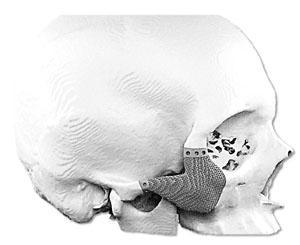

Medicad Implants is a state of the art technology firm specialized in providing customized solutions for hard tissue replacement and cranial implant in India. We are a synergy of motivated and experienced Engineers, Medical Practitioners and Designers striving to help surgeons for cranial implant india for their patients.

Patient specific” Technology is one of the latest development in the medical field aimed at providing more accurate and lasting healthcare to patients. It synergically ties the medical imaging techniques with reverse engineering and rapid manufacturing concepts long being used in Aerospace and automobile fields to provide a unique solution on a case by case basis.